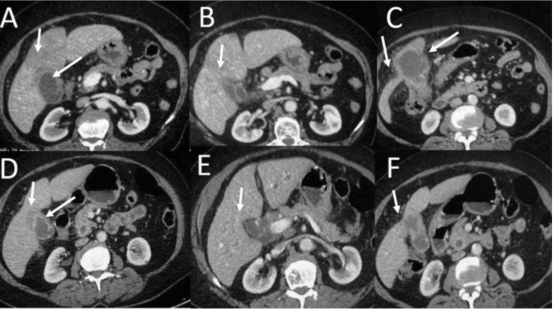

局部晚期胆囊癌Abdom Radiol 46, 998–1007 (2021)

在增强扫描过程中,不同性质的病变具有不同的强化特点。胆囊恶性肿瘤通常在动脉期呈现明显强化,门静脉期及延迟期强化程度逐渐下降。这种强化模式与良性病变如胆囊炎、胆囊息肉等有一定区别,有助于鉴别诊断。例如,胆囊炎主要表现为胆囊壁的均匀增厚和强化,而胆囊癌则可能出现不规则增厚、结节状强化以及向周围组织侵犯的表现。